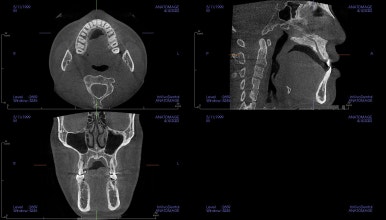

이런 유형의 환자분에서 당연히 예상되는 호흡기 문제도 체크해 주고요.

우선은 악궁확장장치를 합니다.

악궁확장은 언제 해야 되는가? 성인은 모두 미니스크류를 이용해야 하는가?(MARPE?)

악궁확장은 단순히 윗니가 삐뚤다고 하는 것도 아니고, 주걱턱이라고 하는 것도 아닙니다.

아래턱에 비해서 위턱이 좁을 때 하는 것이고요.

성인이라고 모두 미니스크류를 이용한 악궁확장장치(MARPE)를 하는 건 아니며, 여러 가지 분석법으로 성인에서도 일반 악궁확장장치(RPE) 성공 가능성이 높은 환자분은 일반 확장장치를 사용하고 있습니다.

아무튼 이번 환자분은 위턱 자체가 폭이 좁아서 확장을 먼저 진행했고요.